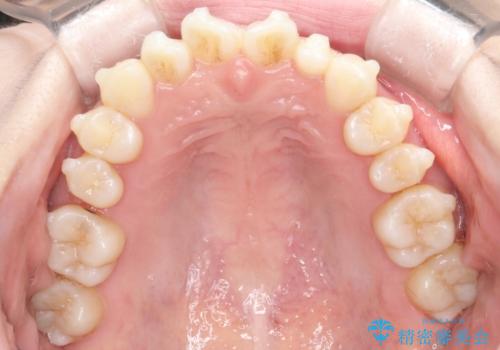

【インビザライン】矮小歯を有する方の治療②

- 前歯の凸凹を主訴に来院されました。

左上の前歯が元々小さいため、前歯の真ん中が揃わないことを伝えた上で矯正治療を開始しています。

スペースを作るために遠心移動ろIPRをおこなて治療を行いました。